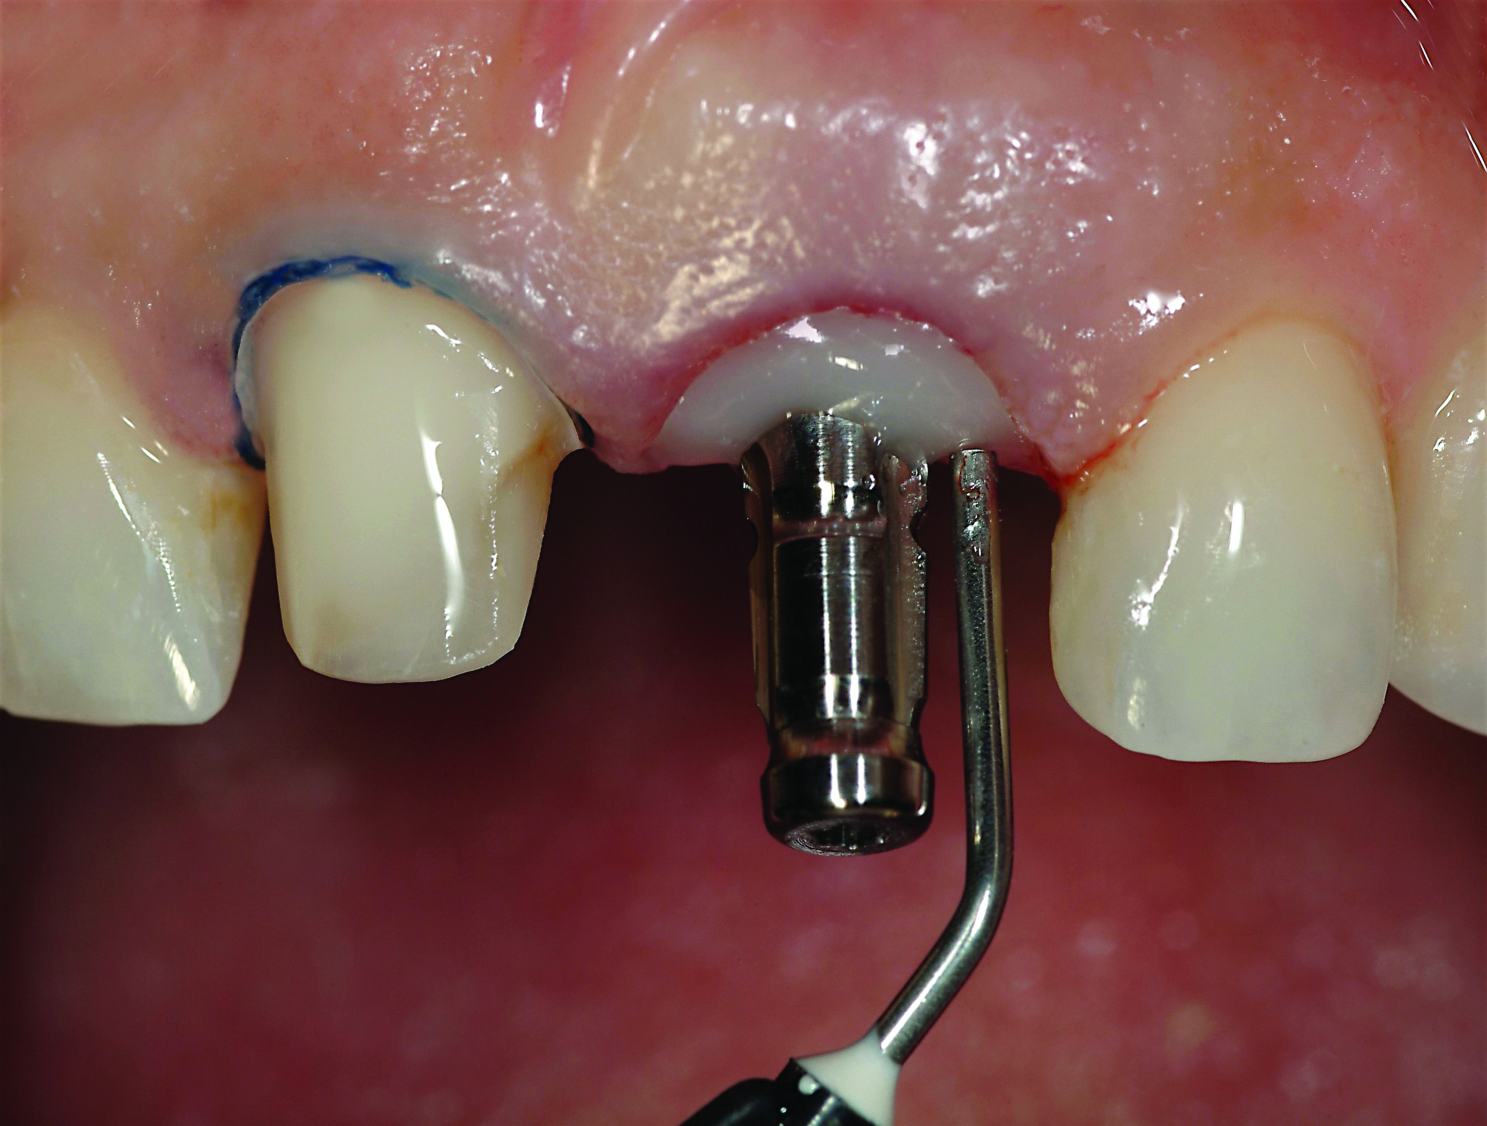

Fig 16. A screw-retained provisional restoration being delivered within 1 week of surgery is used to guide the soft-tissue architecture during the period of osseointegration.

Figure 16